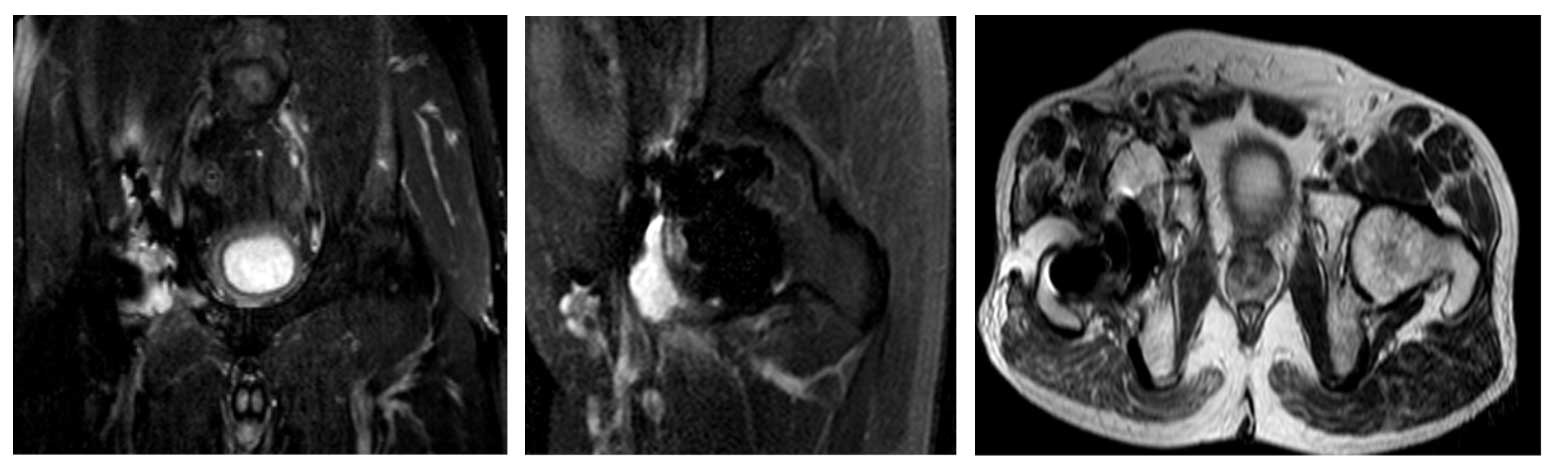

Ameliyat Öncesi: MR’da tümör nüksü teyit edilmekte.